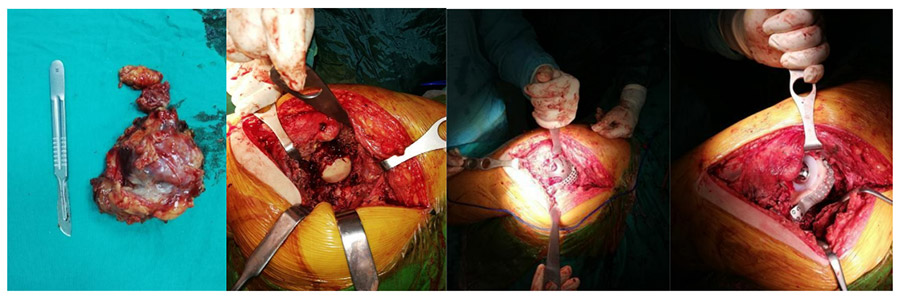

During the operation: The image shows the removal of tumor tissue, reconstruction of the remaining space with titanium anatomical plates and cages, and the application of a cemented hip prosthesis.